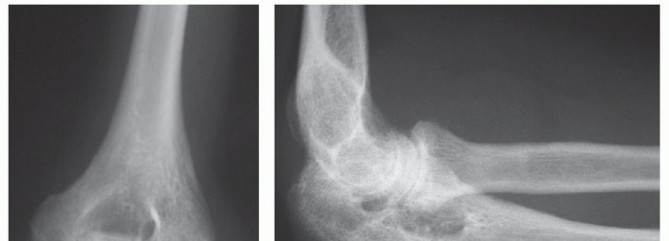

Distal Humeral Fractures: When Is Elbow Replacement the Best Option?